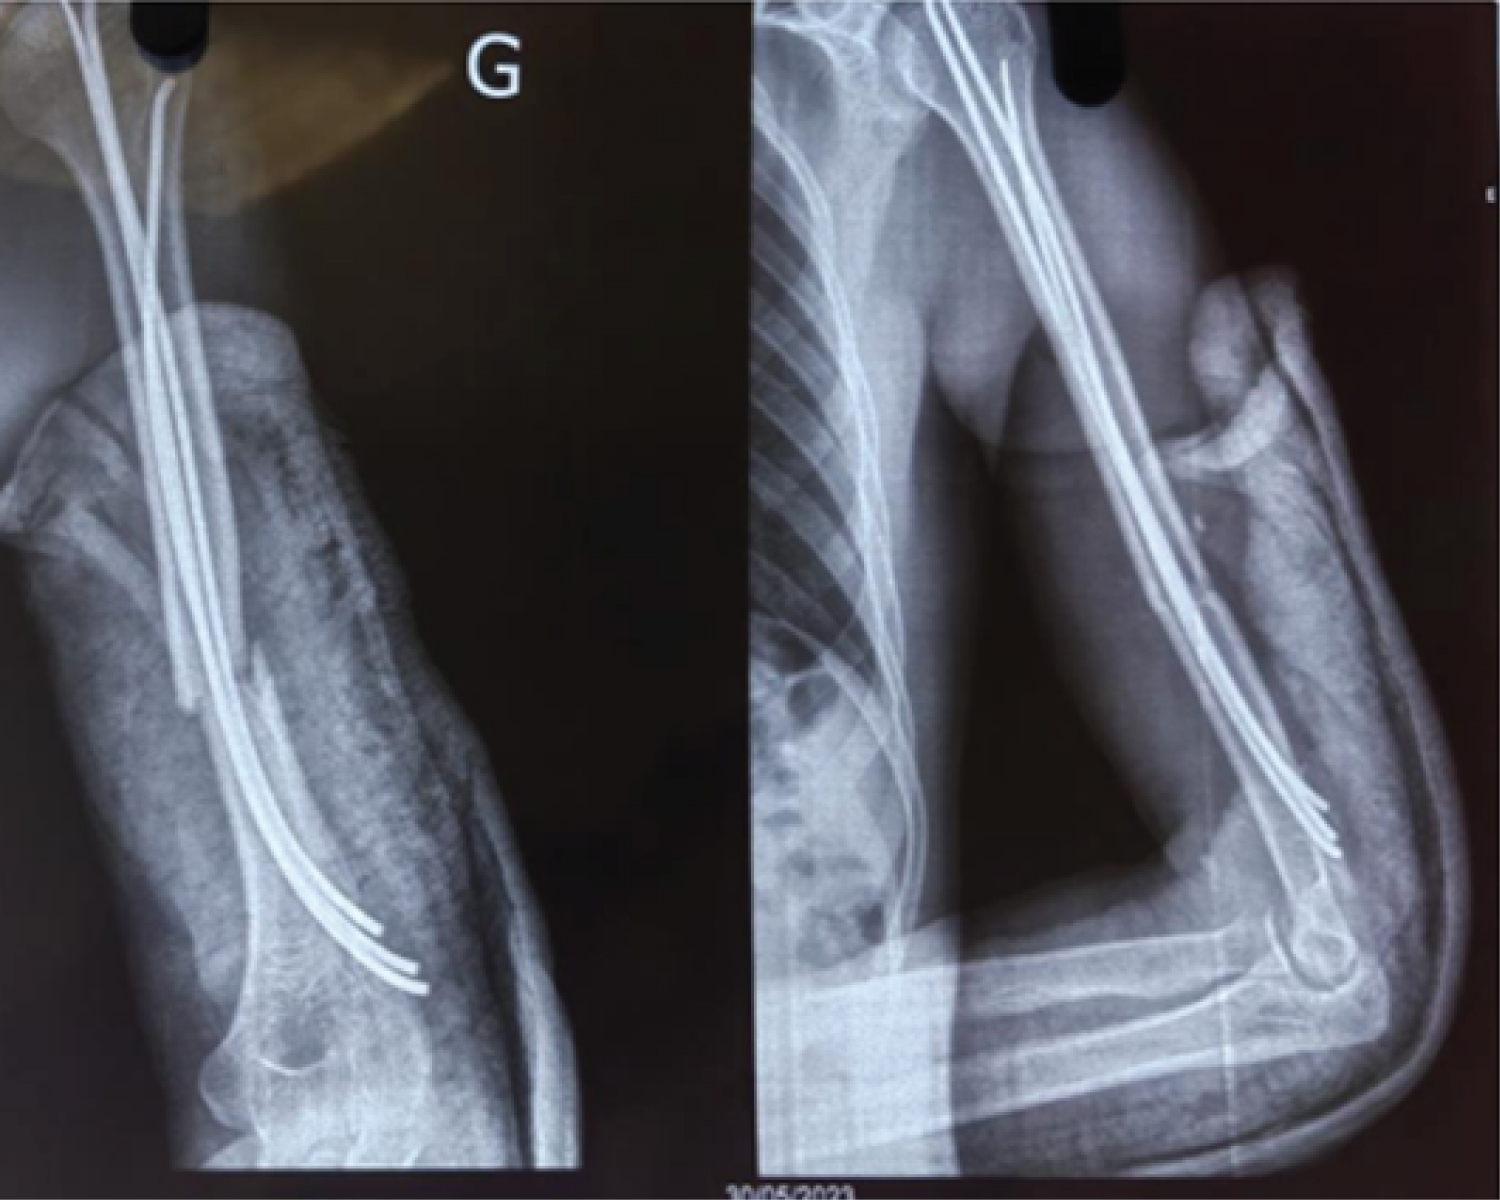

We conducted a descriptive cross-sectional study over a 54-month period from January 2019 to June 2023 at the Orthopedic and Trauma Surgery Department (SCOT) of the Renaissance University Hospital. All patients aged 18 or over who underwent surgery and were followed up at SCOT during the study period and had a usable clinical record were included. Patients treated by other surgical procedures and orthopedically, as well as those with incomplete clinical records, were excluded from our study. The AO classification was used for bone lesions and the Gustillo/Anderson (G/A) classification for skin opening. All patients were positioned supine on a standard table under general anaesthesia, with the fractured limb placed on a radiolucent table. Reduction was performed by external maneuvering under the control of a mobile image intensifier, parallel to the operating table. The supra-olecranial approach through an oval hole was used to insert Metaizeau wires of various sizes (Figure 1). The pins were inserted into the fracture site and diverged in the humeral head under image intensifier control (Figure 2), and an immediate control radiograph was taken (Figure 3). Epidemiological, radio-clinical, therapeutic and evolutionary variables were studied on the basis of a data sheet and patient summons. Anatomical and functional results were assessed using the STEWARD AND HUNDLEY score.

Figure 2: (a) Left humeral shaft fracture; (b) Wire insertion. View Figure 2

Figure 3: Control X-ray (a) front (b) profile. View Figure 3